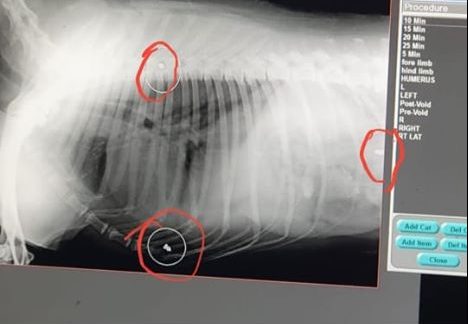

A stray dog near JP Nagar was shot, three bullets says the X-ray report. Admitted to a veterinary hospital in Jayanagar, doctors yet to remove bullets @Sowmyareddyr@NewIndianXpress

Senior Veterinarian, Dr. Sathish reported that they performed an x-ray on the dog and it showed three bullets from an air gun lodged in her body. They stabilized the dog first and then they will go for surgery. They couldn’t perform surgery as the dog was in a state of shock.